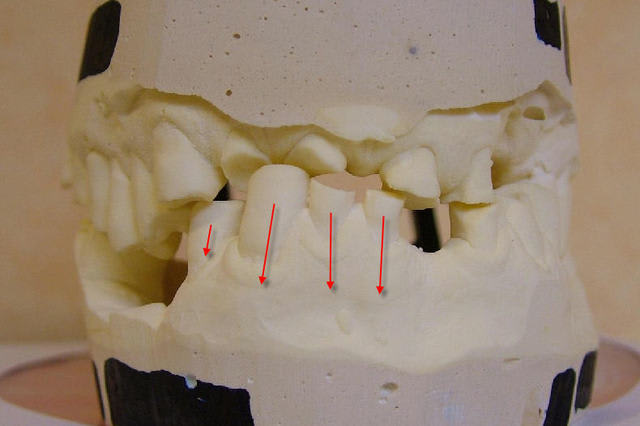

avant de faire le wax up, j'aurai fait une prise d'arc facial, montage sur articulateur et une technique du drapeau pour me donner une idée plus précise du plan d'occlusion "idéal".

Peut être faudrait-il virer certaines dents mandibulaires, peu intéressantes d'un point de vue prothétique pour être plus en conformité avec ce plan d'occlusion idéal. Je pense en particulier aux 3 incisives mandibulaires.

La fonte osseuse liée à ces extractions + une éventuelle plastie permettrait de gagner encore un peu de place; mais aussi permettrait d'harmoniser le sourire (avec 4 incisives prothétiques) et de rétablir une occlusion antérieure conventionnelle et non pas en bout à bout (en plus la résorption osseuse mandibulaire antérieure s'effectue de façon centripéte).

C'est sur qu'a mon avis l'ingression des Inc mandibulaire serait le meilleure choix.

Calages tsbyyu - Eugenol

Courbes eu2yz4 - Eugenol

Wahouuuu! trop fort cingulum pour tracer virtuellement la courbe d'occlusion... ;)

Super tes photos solene,

la mise en occluseur me parait erronée avec ce type d'abrasions les incisives devraient être en contact, mais pas grave l'essentiel c'est l'aperçu. ,

Je mettrai la semaine prochaine les photos des modèles avec la nouvelle occlusion.